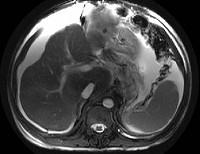

男,44岁,有乙肝病史,现腹胀,右上腹痛,消化不良,消瘦、乏力、贫血、黄疸,血清转氨酶升高,清蛋白/球蛋白比值倒置。CT、MRI检查如下图,最准确的诊断是...

问题 男,44岁,有乙肝病史,现腹胀,右上腹痛,消化不良,消瘦、乏力、贫血、黄疸,血清转氨酶升高,清蛋白/球蛋白比值倒置。CT、MRI检查如下图,最准确的诊断是 ( )

选项 A.肝硬化并腹水 B.肝硬化并腹水、再生结节 C.肝硬化腹水、肝癌 D.肝硬化并再生结节 E.肝硬化并腹水、脂肪肝

答案 B